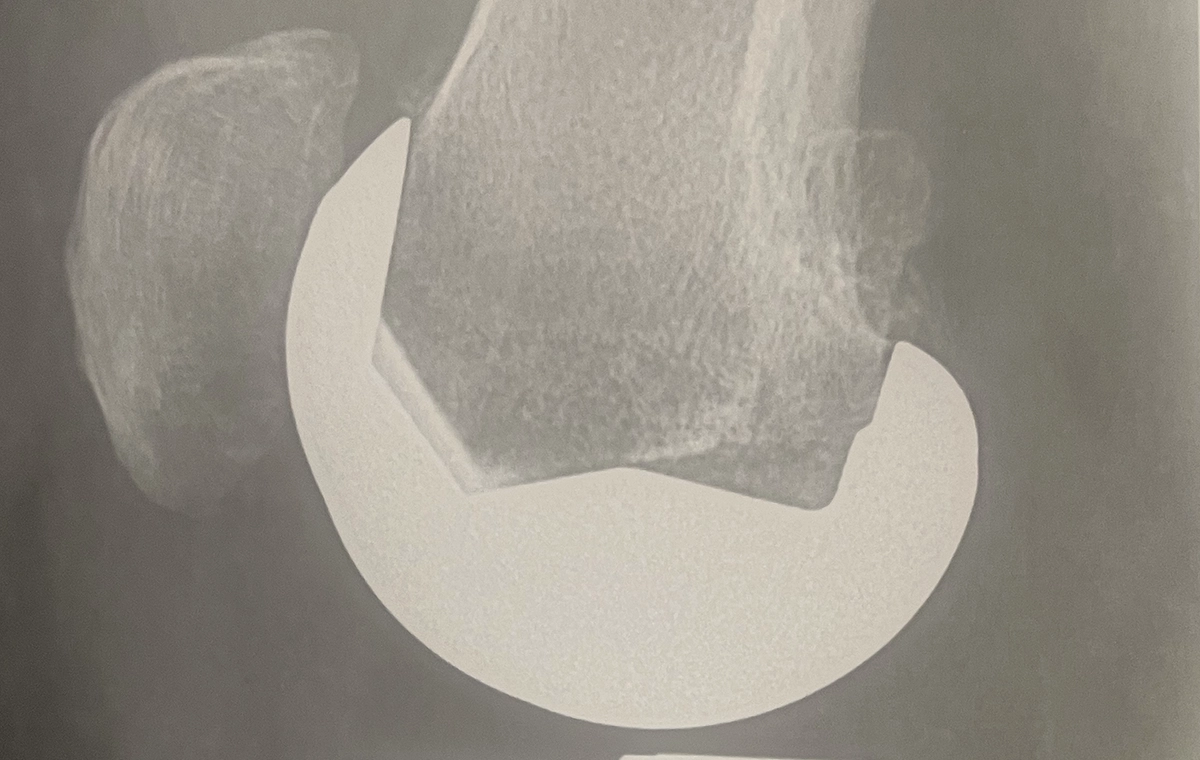

Dans une prothèse sur mesure, la pièce fémorale est fabriquée pour le fémur du patient (photo ci-dessous) (idem pour le tibia).

Pièce fémorale sur mesure Origin symbios

Les radios de la prothèse sur mesure Origin

De face (première image) : vous pouvez voir que la pièce prothètique recouvre parfaitement la surface osseuse et que la tige tibiale est plus longue, conformément au choix du chirurgien.

Radio de face d'une prothèsee totale du genou

Radio d'une prothèse de genou Origin sur mesure